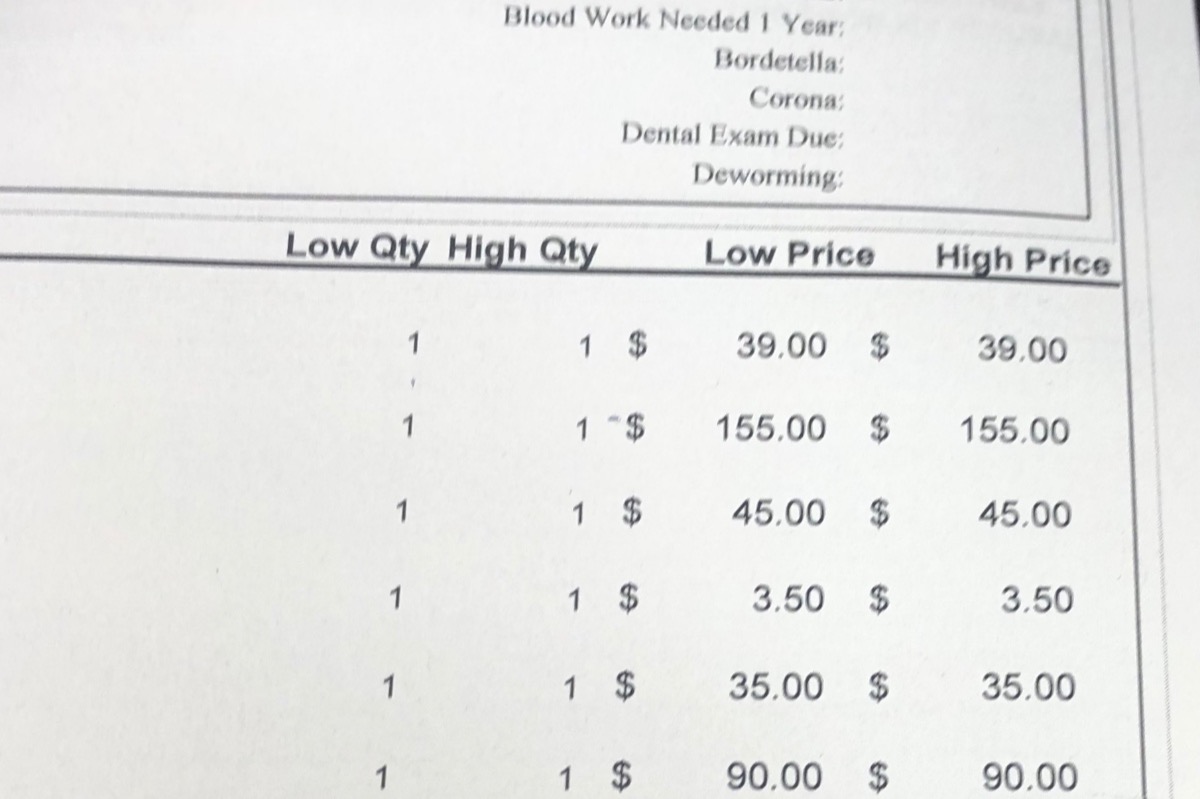

The vet bills are no joke

Initial vet appointment and bill

The vet bills are no joke

Initial vet appointment and bill